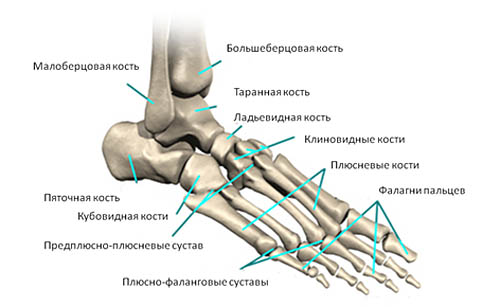

Перелом – это довольно серьёзная травма, которая, к сожалению, в медицинской практике встречается довольно часто. Из всех случаев около 3% занимают переломы плюсневых костей, располагающихся в стопе. А какими особенностями отличается восстановление после перелома плюсневой кости? Какими последствиями может быть опасна такая травма?

Перелом плюсневой кости занимает практически первое место среди всех травм стопы. Эти кости располагаются в передней части основания ступни и являются довольно хрупкими. А частые нагрузки и прочие факторы приводят к повреждениям.

Данные травмы можно классифицировать по нескольким показателям. Так, если сломана одна кость, то речь идёт об одиночном переломе, если затронуты 2 и более костей, то это множественный перелом. Повреждаться могут разные части: диафиз, основание или шейка. Различными могут быть и сами повреждения в зависимости от локализации и формы. В частности, линия надлома может быть поперечной, косой, Т-образной или клиновидной. От таких особенностей зависит лечение и период реабилитации

Всего плюсневых костей пять. Наиболее частым является перелом 5 или 4-й плюсневой кости стопы, так как они являются наиболее хрупкими и уязвимыми. Реже встречаются переломы 1 кости и совсем редко 2 и 3-й. Что касается пятой кости, то её травмирование часто осложняется смещением и выходом за плоскость ступни.